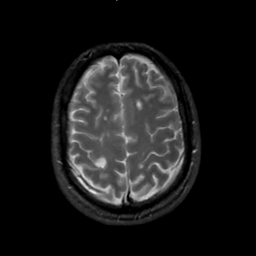

MR Study #2, February 17, 1991 -- Slice #39

[Home][Help][Clinical][Tour 1][Tour 2] Slice 39